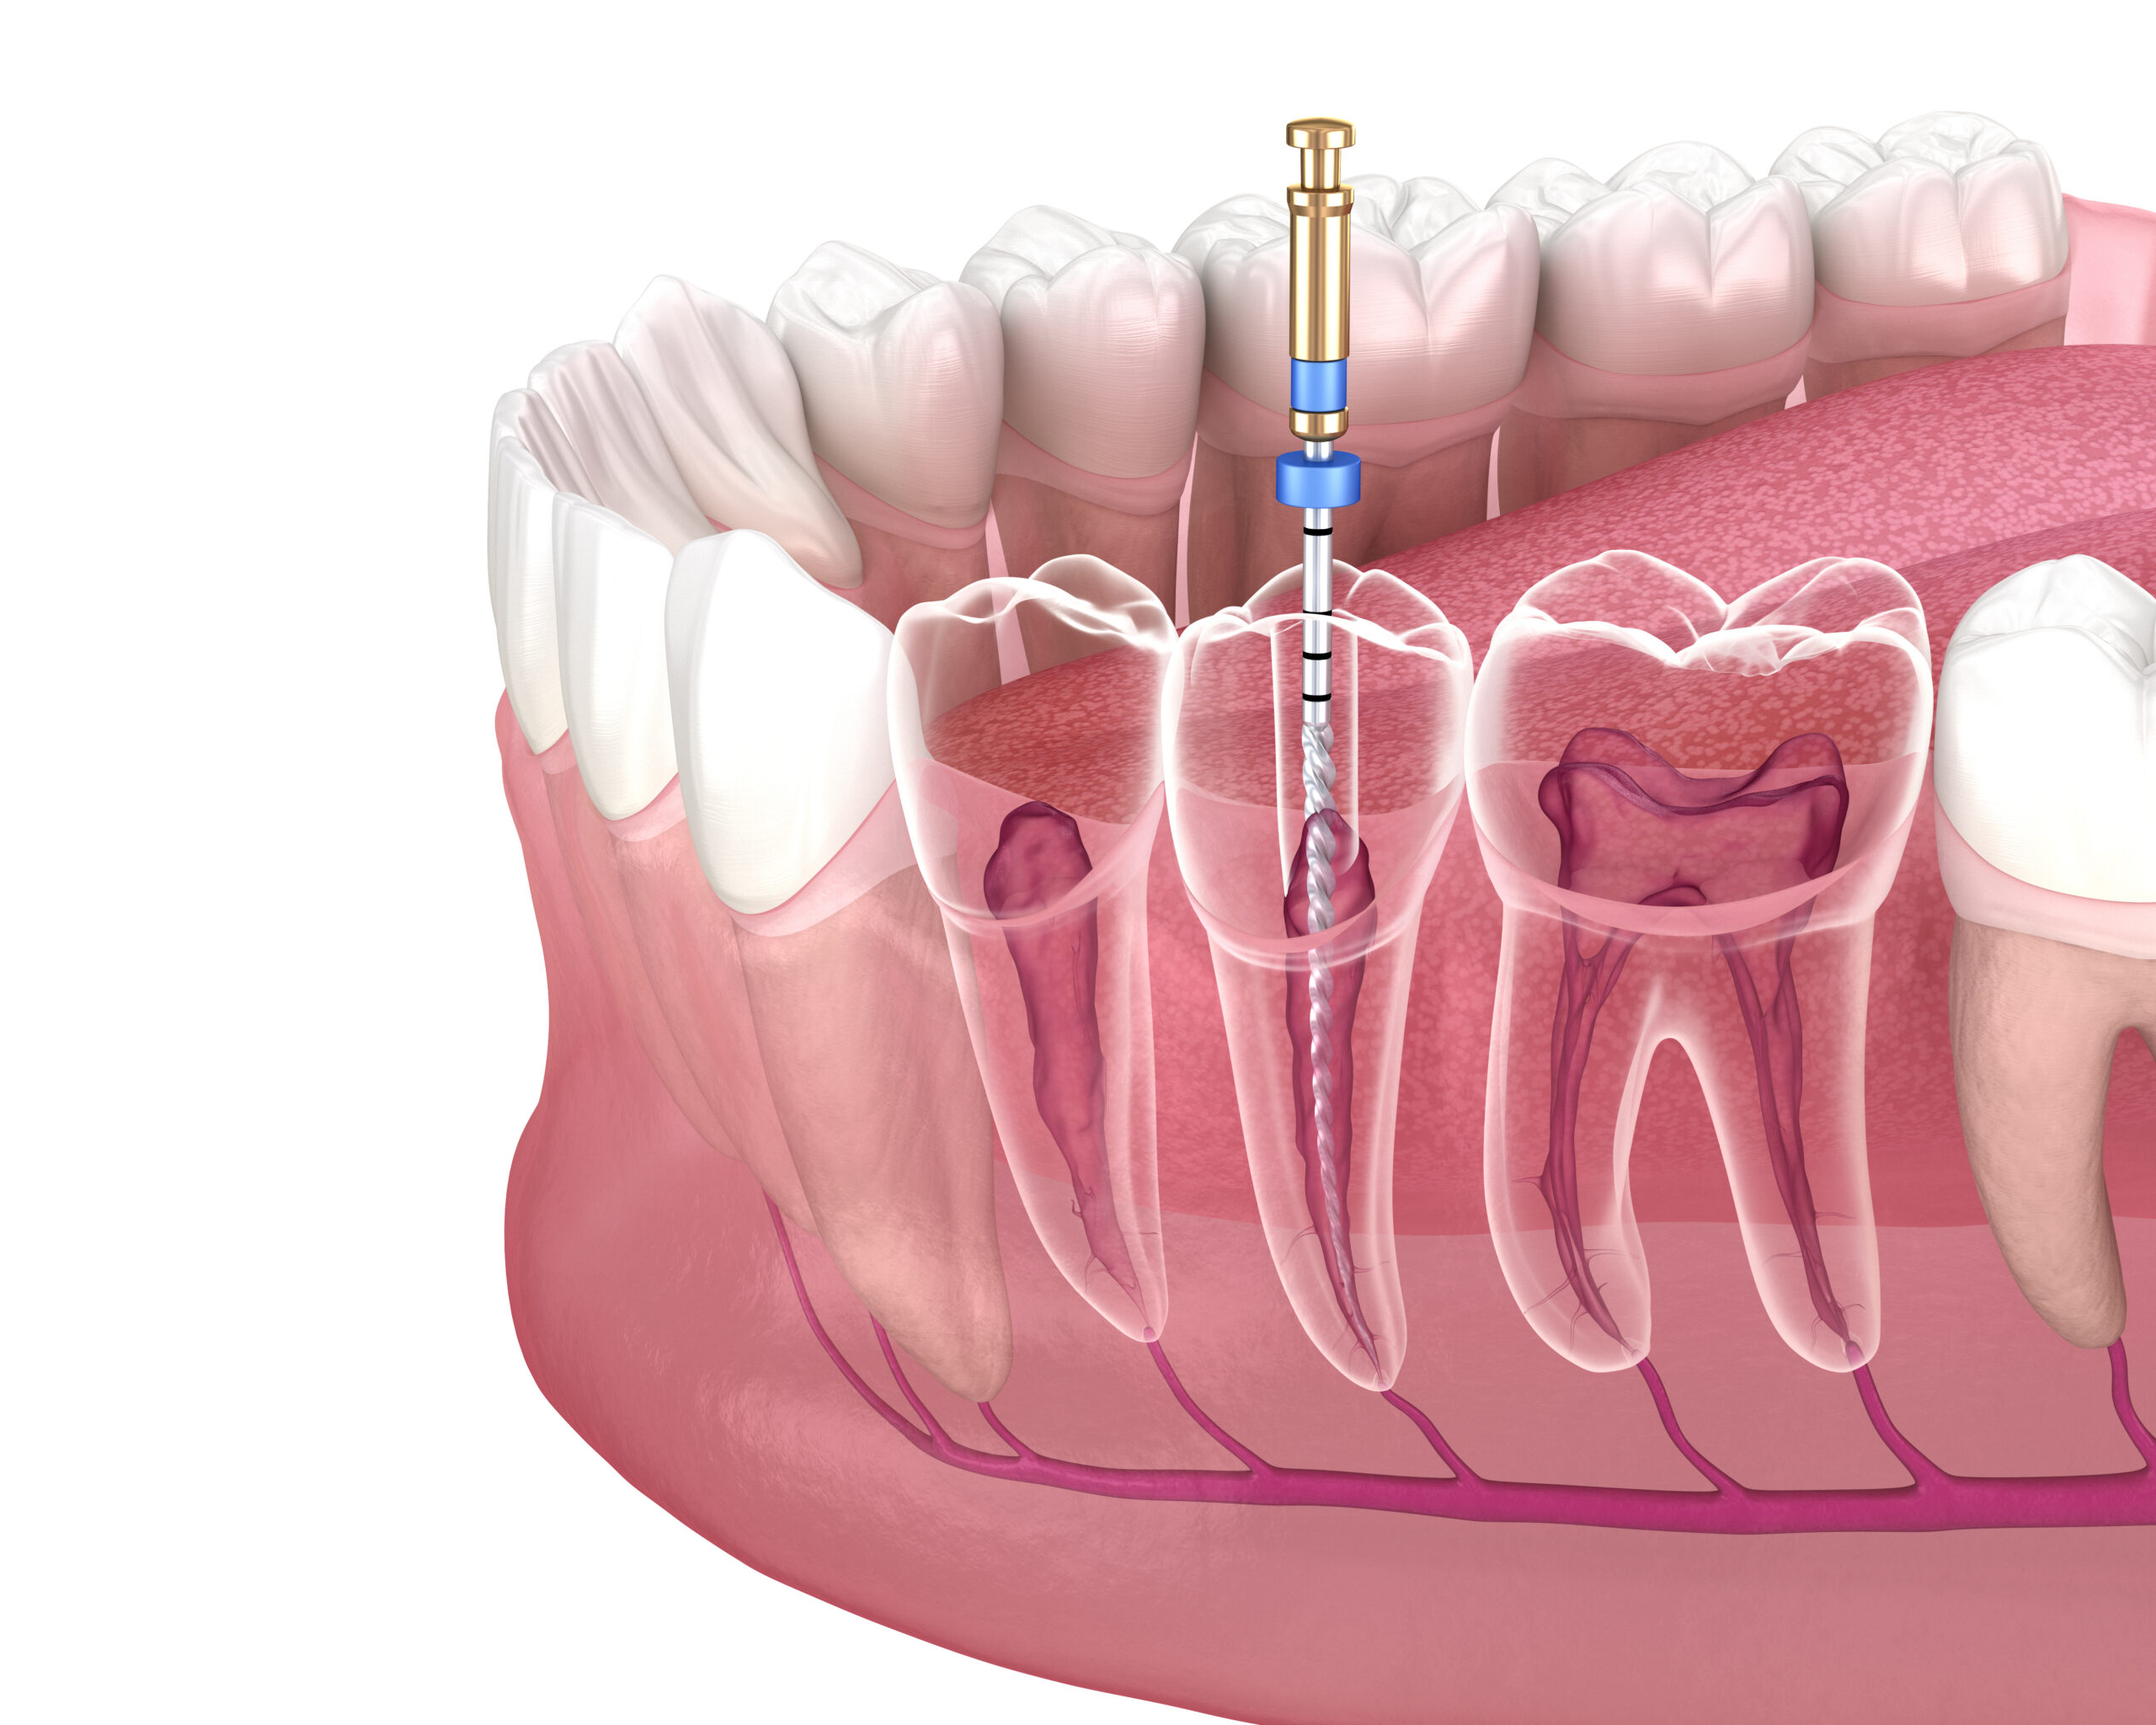

Tedavilerimiz

Her biri alanında uzman hekimlerimizle, en son teknolojileri kullanarak kapsamlı diş sağlığı hizmetleri sunuyoruz.